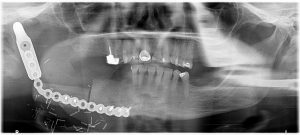

Removal of impacted teeth Surgical removal of all wisdom teeth and impacted teeth. An impacted tooth is a tooth that is unable to erupt into its normal position in the jaw. This is usually caused by the tooth becoming blocked in-between two adjacent teeth or by the tooth being formed in an abnormal position. The most commonly affected teeth are the wisdom teeth/third molars and the canines. Wisdom teeth are the last teeth to erupt in your mouth, usually between the ages of 17 and 25. In ancient times, the rough diet people followed resulted in the excessive wear of their teeth. The normal drifting of the teeth to compensate for this wear ensured that space was available for most wisdom teeth to erupt by adolescence. However, our modern diet is softer, so wear is minimal so drift is also minimal, resulting in less space for wisdom teeth to erupt naturally. Why remove them? If a wisdom tooth doesn’t have room to grow (impacted wisdom tooth), this may result in pain, infection or other dental problems. The patient will then probably need to have it removed. The extraction of wisdom teeth is generally necessary when they are prevented from properly erupting within the mouth. Poor alignment of wisdom teeth can crowd or damage adjacent teeth, the jawbone, and nerves. Wisdom teeth that lean toward the second molars make those teeth more vulnerable to decay by entrapping plaque and debris. This can lead to swollen and sore gums (pericoronitis), tooth decay, jaw stiffness and infection. Partially erupted teeth are also more prone to tooth decay and gum disease because their hard-to-reach location and awkward positioning makes brushing and flossing difficult. Other issues that can arise include the formation of tumours or cysts around the impacted tooth. This can in turn result in permanent damage to the jawbone and other, healthy teeth. What happens next? Dr Ehlers will exam and take an X-Ray of your mouth. This will allow him to see the extent of the impaction or eruption and to plan a course of action suitable to your particular case. Depending on his assessment Dr Ehlers will advise you on whether it is better to have a procedure where local anaesthetic (you will be awake during the procedure) is used or general anaesthetic (you will be asleep during the procedure). During a local anaesthetic procedure your gum area will be numbed around the wisdom tooth/teeth, so you will feel no pain. In addition, Dr Ehlers may opt to use a sedative which will help you to relax during the procedure. During the procedure, the tooth may be cut into smaller parts to make it easier to remove through the opening. There’s less need to make an incision if the tooth has already erupted through the gum. Should you need to be admitted to hospital as a day patient, you will be given a general anaesthetic which will make you sleep. Read more about after-procedure care